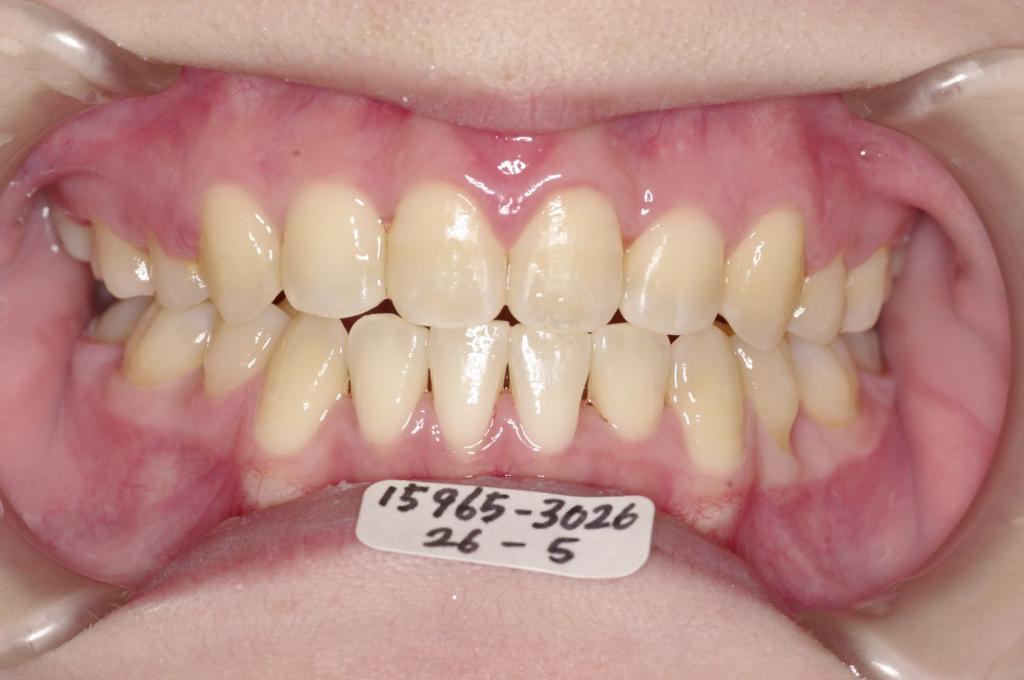

前歯、出っ歯・開咬の矯正治療

(治療期間、治療前後写真、治療方法、費用)WORKS